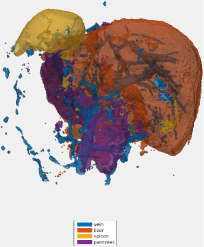

Testing: Our test set is different from our training and validation data. It originates from a different hospital, scanner, and research study with gastric cancer patients. 150 abdominal CT scans were acquired in the portal venous phase. Each CT volume consists of slices of pixels. Voxel dimensions are [0.55-0.82, 0.55-0.82, 0.4-0.80] mm. The pancreas, liver, and spleen were semi-automatically delineated by three trained researchers and confirmed by a clinician. Figure 4 shows surface renderings for comparison of the different stages of the algorithm. A typical testing case in the first and second stages is shown using non-overlapping and overlapping tiles (Eq. 4). Dice similarity scores are listed in Table 2. This dataset provides slightly higher image quality than our training/validation dataset. Furthermore, its field of view is slightly more constrained to the upper abdomen. This probably explains the better performance for liver and pancreas compared to the validation set in Table 1.